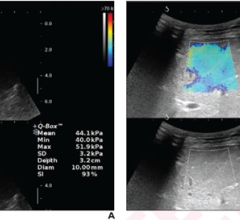

April 4, 2023 — Ultrasound is an effective standalone diagnostic method in patients with focal breast complaints ...